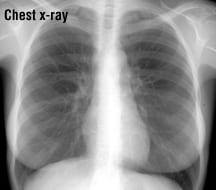

X-rays are waves of electromagnetic radiation that are used to create images of organs and other structures inside the body. X-rays have a very short wavelength. As they penetrate the body, they are absorbed in different amounts by different body tissues. For example, bones are dense and absorb X-rays very well, but soft tissues (skin, fat, muscle) allow more X-rays to pass through. The result is an X-ray shadow on a film or fluorescent screen, where images of bones appear white, while shadows of soft tissues appear as various shades of gray.

X-rays are used for many purposes, including determining if a bone is broken, seeing whether an internal organ is infected, and looking for cancer. There are many different types of X-rays currently used to detect cancer. For example, both mammography (a series of breast X-rays) and the barium enema (a series of bowel X-rays with contrast medium), are routine procedures sometimes used for cancer screening in adults of certain age groups. To check for tumors in precise cross-sections of the body, a computed tomography (CT) scan also can be used. A CT scan is a series of X-rays linked to computer technology. Even without using specialized techniques, uncomplicated, routine X-rays often can show abnormal shadows or silhouettes that might be cancerous tumors.